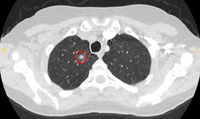

PET CT scan with 18-fluorodeoxyglucose (18-FDG) showing a high uptake peripheral left lung lesion. Surgical resection confirmed a moderately differentiated squamous cell lung cancer

From the collection of Dr George Tsaknis, MD, PhD, FRCP(London), MRQA, MAcadMEd, PGCert; used with permission